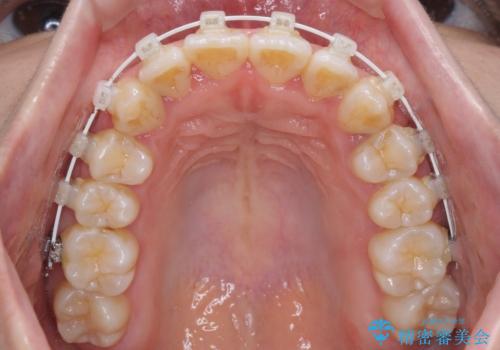

軽微な歯列不正をワイヤー矯正で整える

- 上顎歯列と下顎前歯の叢生を気にして来院された患者様です。

上顎からワイヤー矯正を開始し、終了間際から下顎前歯の叢生解消するよう計画しました。

部分矯正でしたが、咬み合わせに違和感が出ることなく気になる部分を改善させることができました。